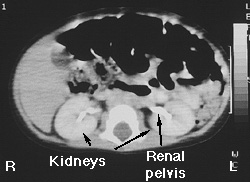

CAT Scan of the Upper Abdomen

Normal Kidneys

This is a contrast CAT scan; intravenous contrast was administered while the images were being obtained. Notice that the kidneys are slightly lighter grey than the adjacent muscle tissue near the vertebral body. This results from the kidney concentrating and excreting iodinated contrast. The renal parenchyma is relatively homogeneous. CAT scans are fairly sensitive indicators of kidney function. If a kidney were not functioning (from lack of perfusion, severe tubular dysfunction, etc.) then the kidneys wouldn't 'enhance' (appear lighter grey). The renal pelvis is white because iodinated contrast has filled the collecting system.